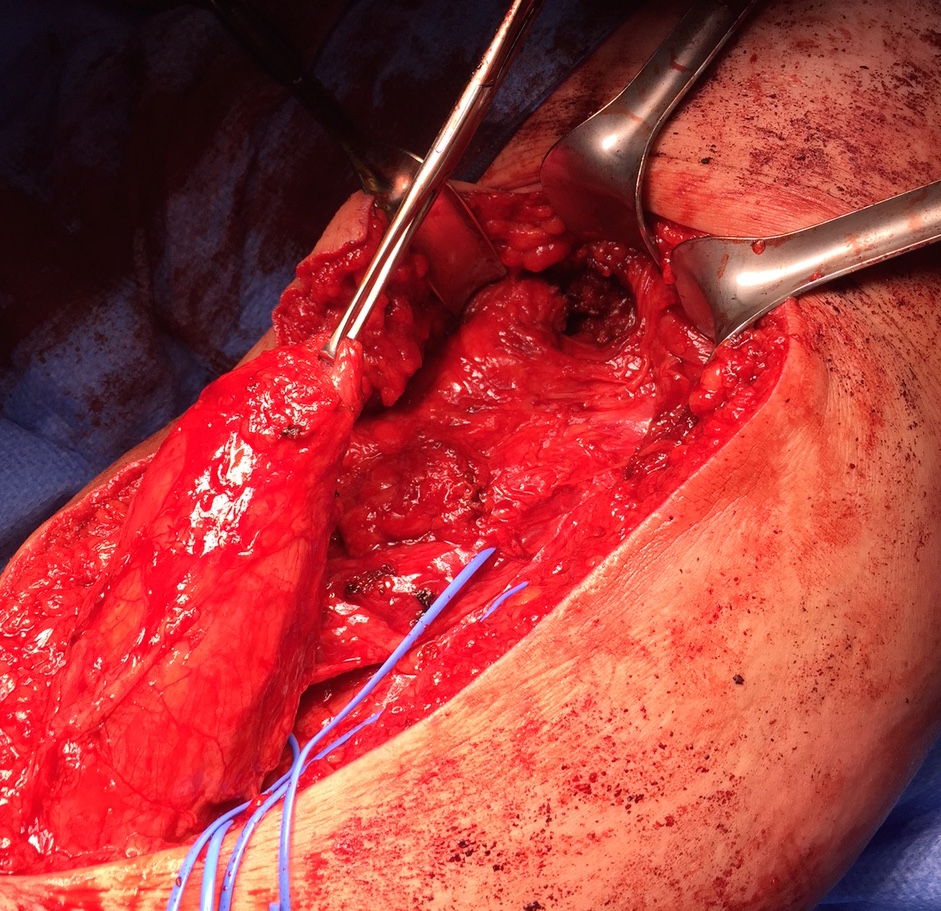

Exposing ischial tuberosity (*) with Cobb retractor

Post suture anchor repair

Ischial tuberosity exposed, then achilles bone block secured with screw